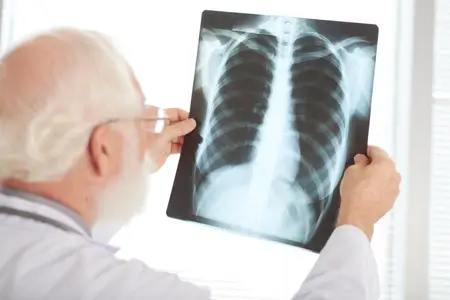

फेफड़ों के कैंसर का निदान कैसे करते हैं?

फेफड़ों के कैंसर के निदान की प्रक्रिया डॉक्टर से बात करने और शारीरिक परीक्षण से शुरू होती है। वे आपके स्वास्थ्य इतिहास और आपके किसी भी लक्षण के बारे में जानना चाहेंगे।

अगर आपको कोई लक्षण है, जो फेफड़ों के कैंसर का संकेत दे सकता है या अगर जांच में कुछ असामान्य दिखाई देता है, तो निदान की पुष्टि के लिए डॉक्टर संभवतः कुछ नैदानिक परीक्षणों की सलाह देंगे। इनमें शामिल हो सकते हैं:

- इमेजिंग परीक्षण: एक्स-रे, एमआरआई, सीटी और पीईटी स्कैन पर एक असामान्य वृद्धि या गांठ को देखा जा सकता है। ये स्कैन और अधिक विस्तृत जानकारी देते हैं और छोटे घावों का पता लगा सकते हैं।